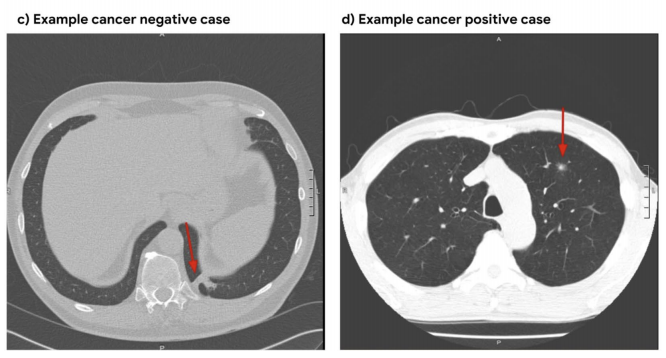

Figure 1: Example cancer-negative case with scarring (left) and example cancer-positive case with a nodule.

Similarly to ardila2019end , we use the National Lung Cancer Trial (NLST) dataset nlst_data , the largest pubicly available chest LDCT dataset, with 25,000 participants. Every CT image in NLST contains pathology-confirmed cancer evaluations (see Figure 1). Image release is limited to 15,000 participants per project, but due to limited storage and compute time, we use a small subset containing 1,493 volumes (34% positive).